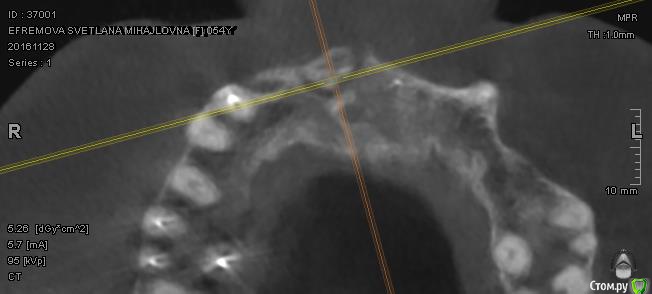

Сделала КТ. Прошу специалистов высказать свое мнение по новым снимкам. Область кости в районе единичек и двойки справа на верхней челюсти.

Можно ли уверенно сказать, что это остеомиелит? и какой вариант лечения посоветуете.

Забыла добавить. Острой боли нет и не было. На протяжении м.б. двух лет иногда бывали эпизоды небольшой ноющей боли, но я связывала это с простудой или переохлаждением. Иногда чувство щекотания или сверления в этой области. А вот последнее время эти симптомы участились.